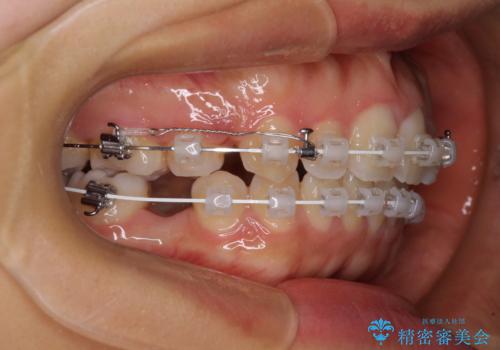

- 審美装置

- 2年2ヶ月

上顎抜歯のみでは奥歯の咬み合わせを改善することが困難であったため、途中で下顎小臼歯も抜歯をしました。

抜歯のタイミングが遅れると治療期間が長期化するため、速やかに抜歯の判断をし、2年強の期間で治療を終えることができました。